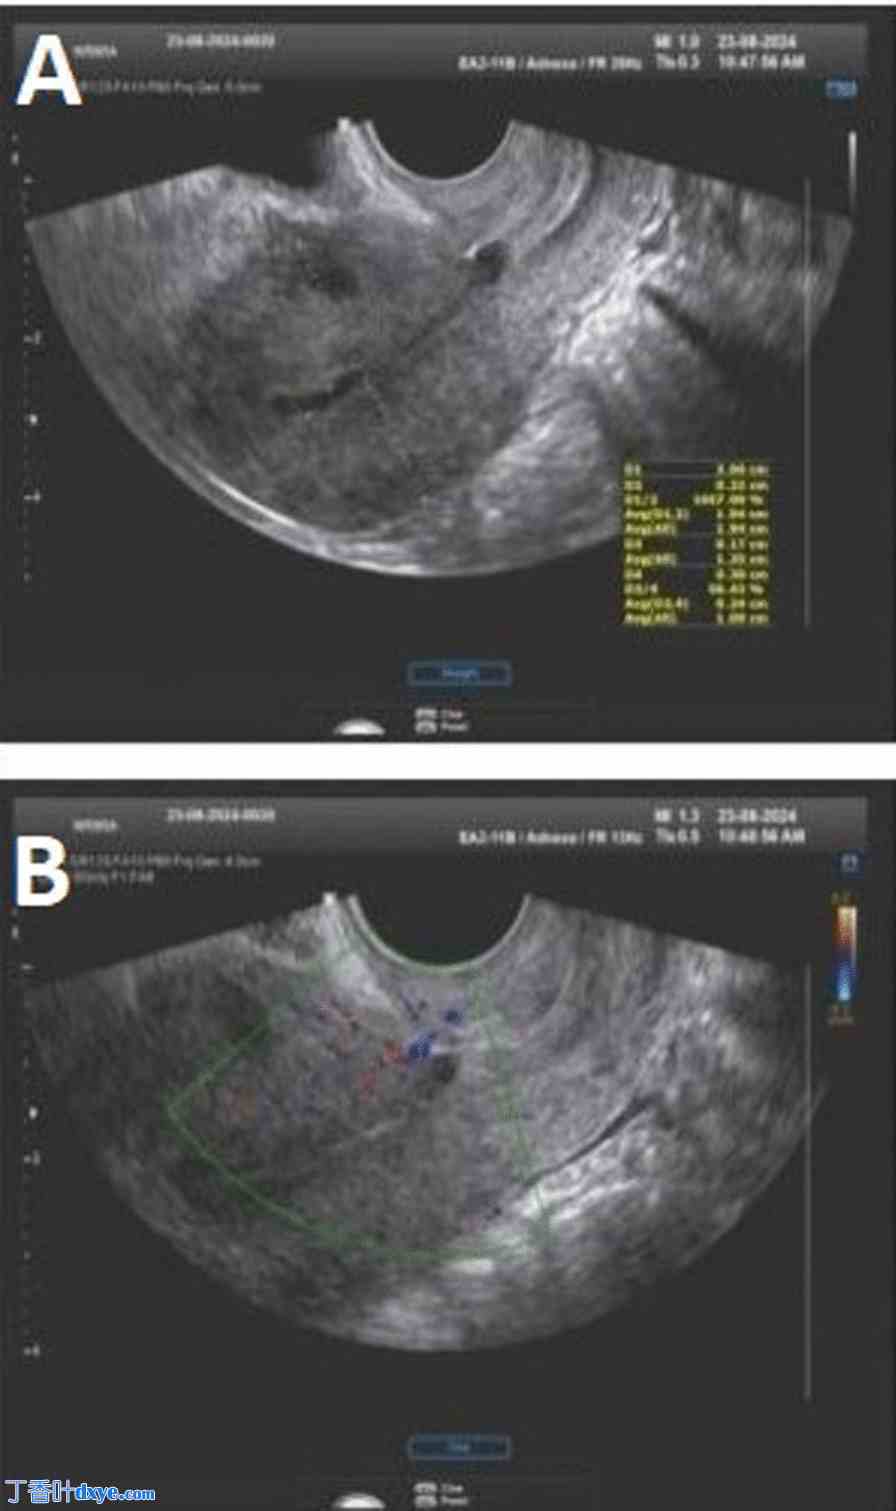

图 7

术后第二周(A)和术后一个月(B)的超声随访中,肿块缩小,血管分布逐渐消失